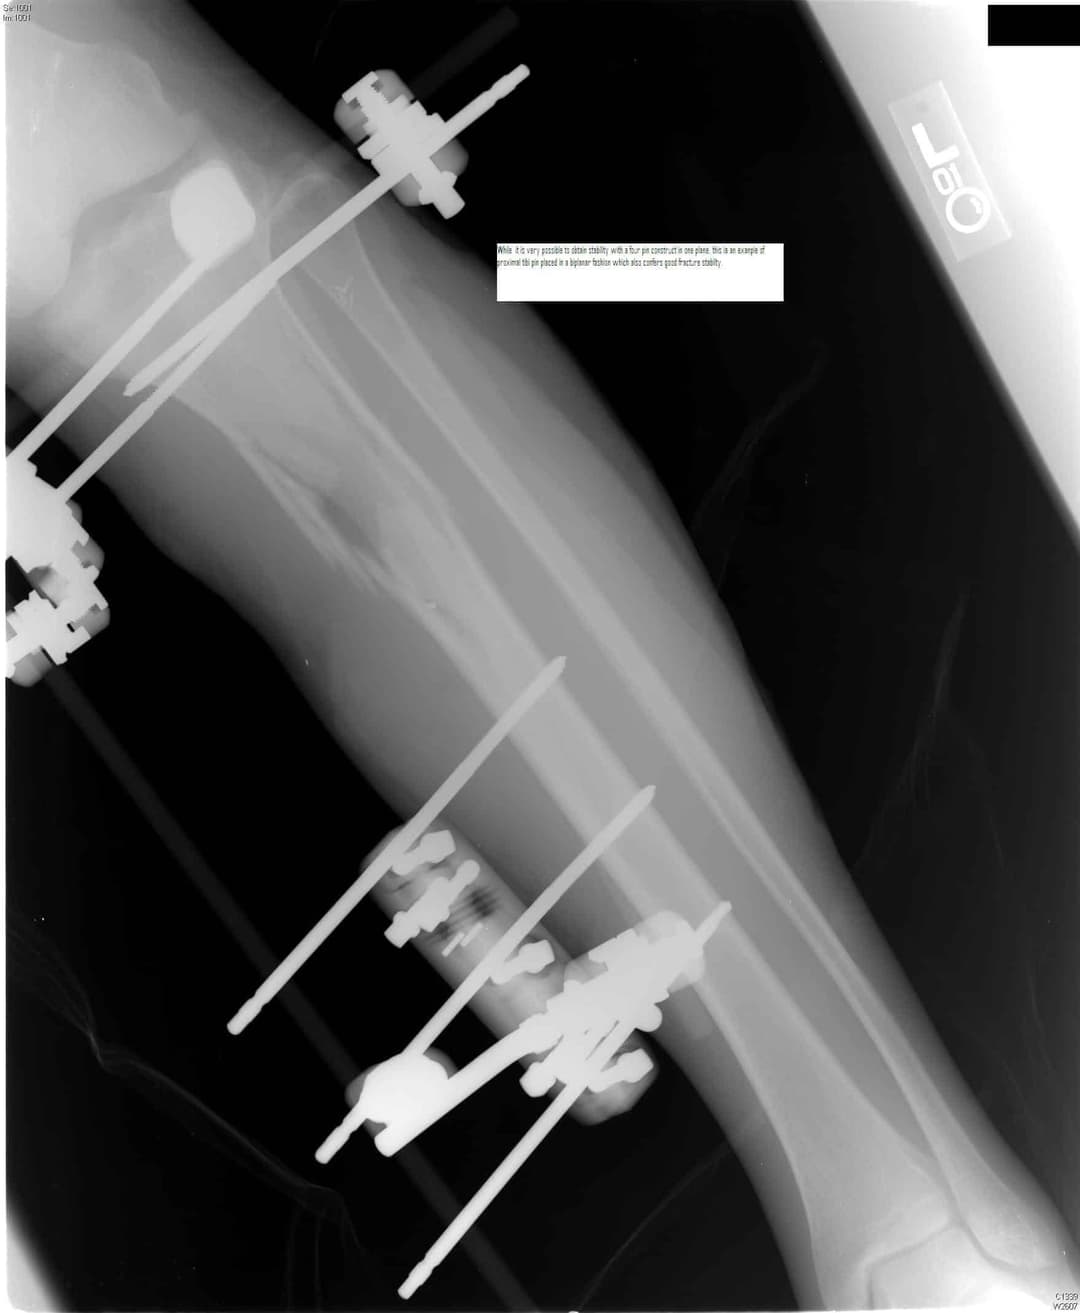

1. див. зобр. 9. Біпланарного контролю також можна досягти за допомогою напівштифтів, встановлених на передньомедіальній та передньолатеральний поверхні проксимального відділу великогомілкової кістки. Зверніть увагу на малогомілковий нерв збоку.

Зобр. 9